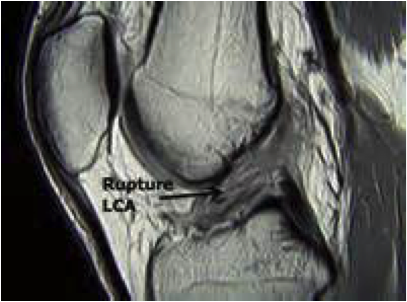

Le diagnostic

Le diagnostic de rupture du ligament croisé antérieur (LCA) peut être évoqué dès l’accident.

Il est habituellement affirmé par l’examen clinique.

Quels sont les examens complémentaires nécessaires ?

Les examens complémentaires vont confirmer le diagnostic, et faire le bilan de lésions associées (ménisques, lésions ligamentaires) :

- Bilan d’imagerie : IRM, Arthroscanner.